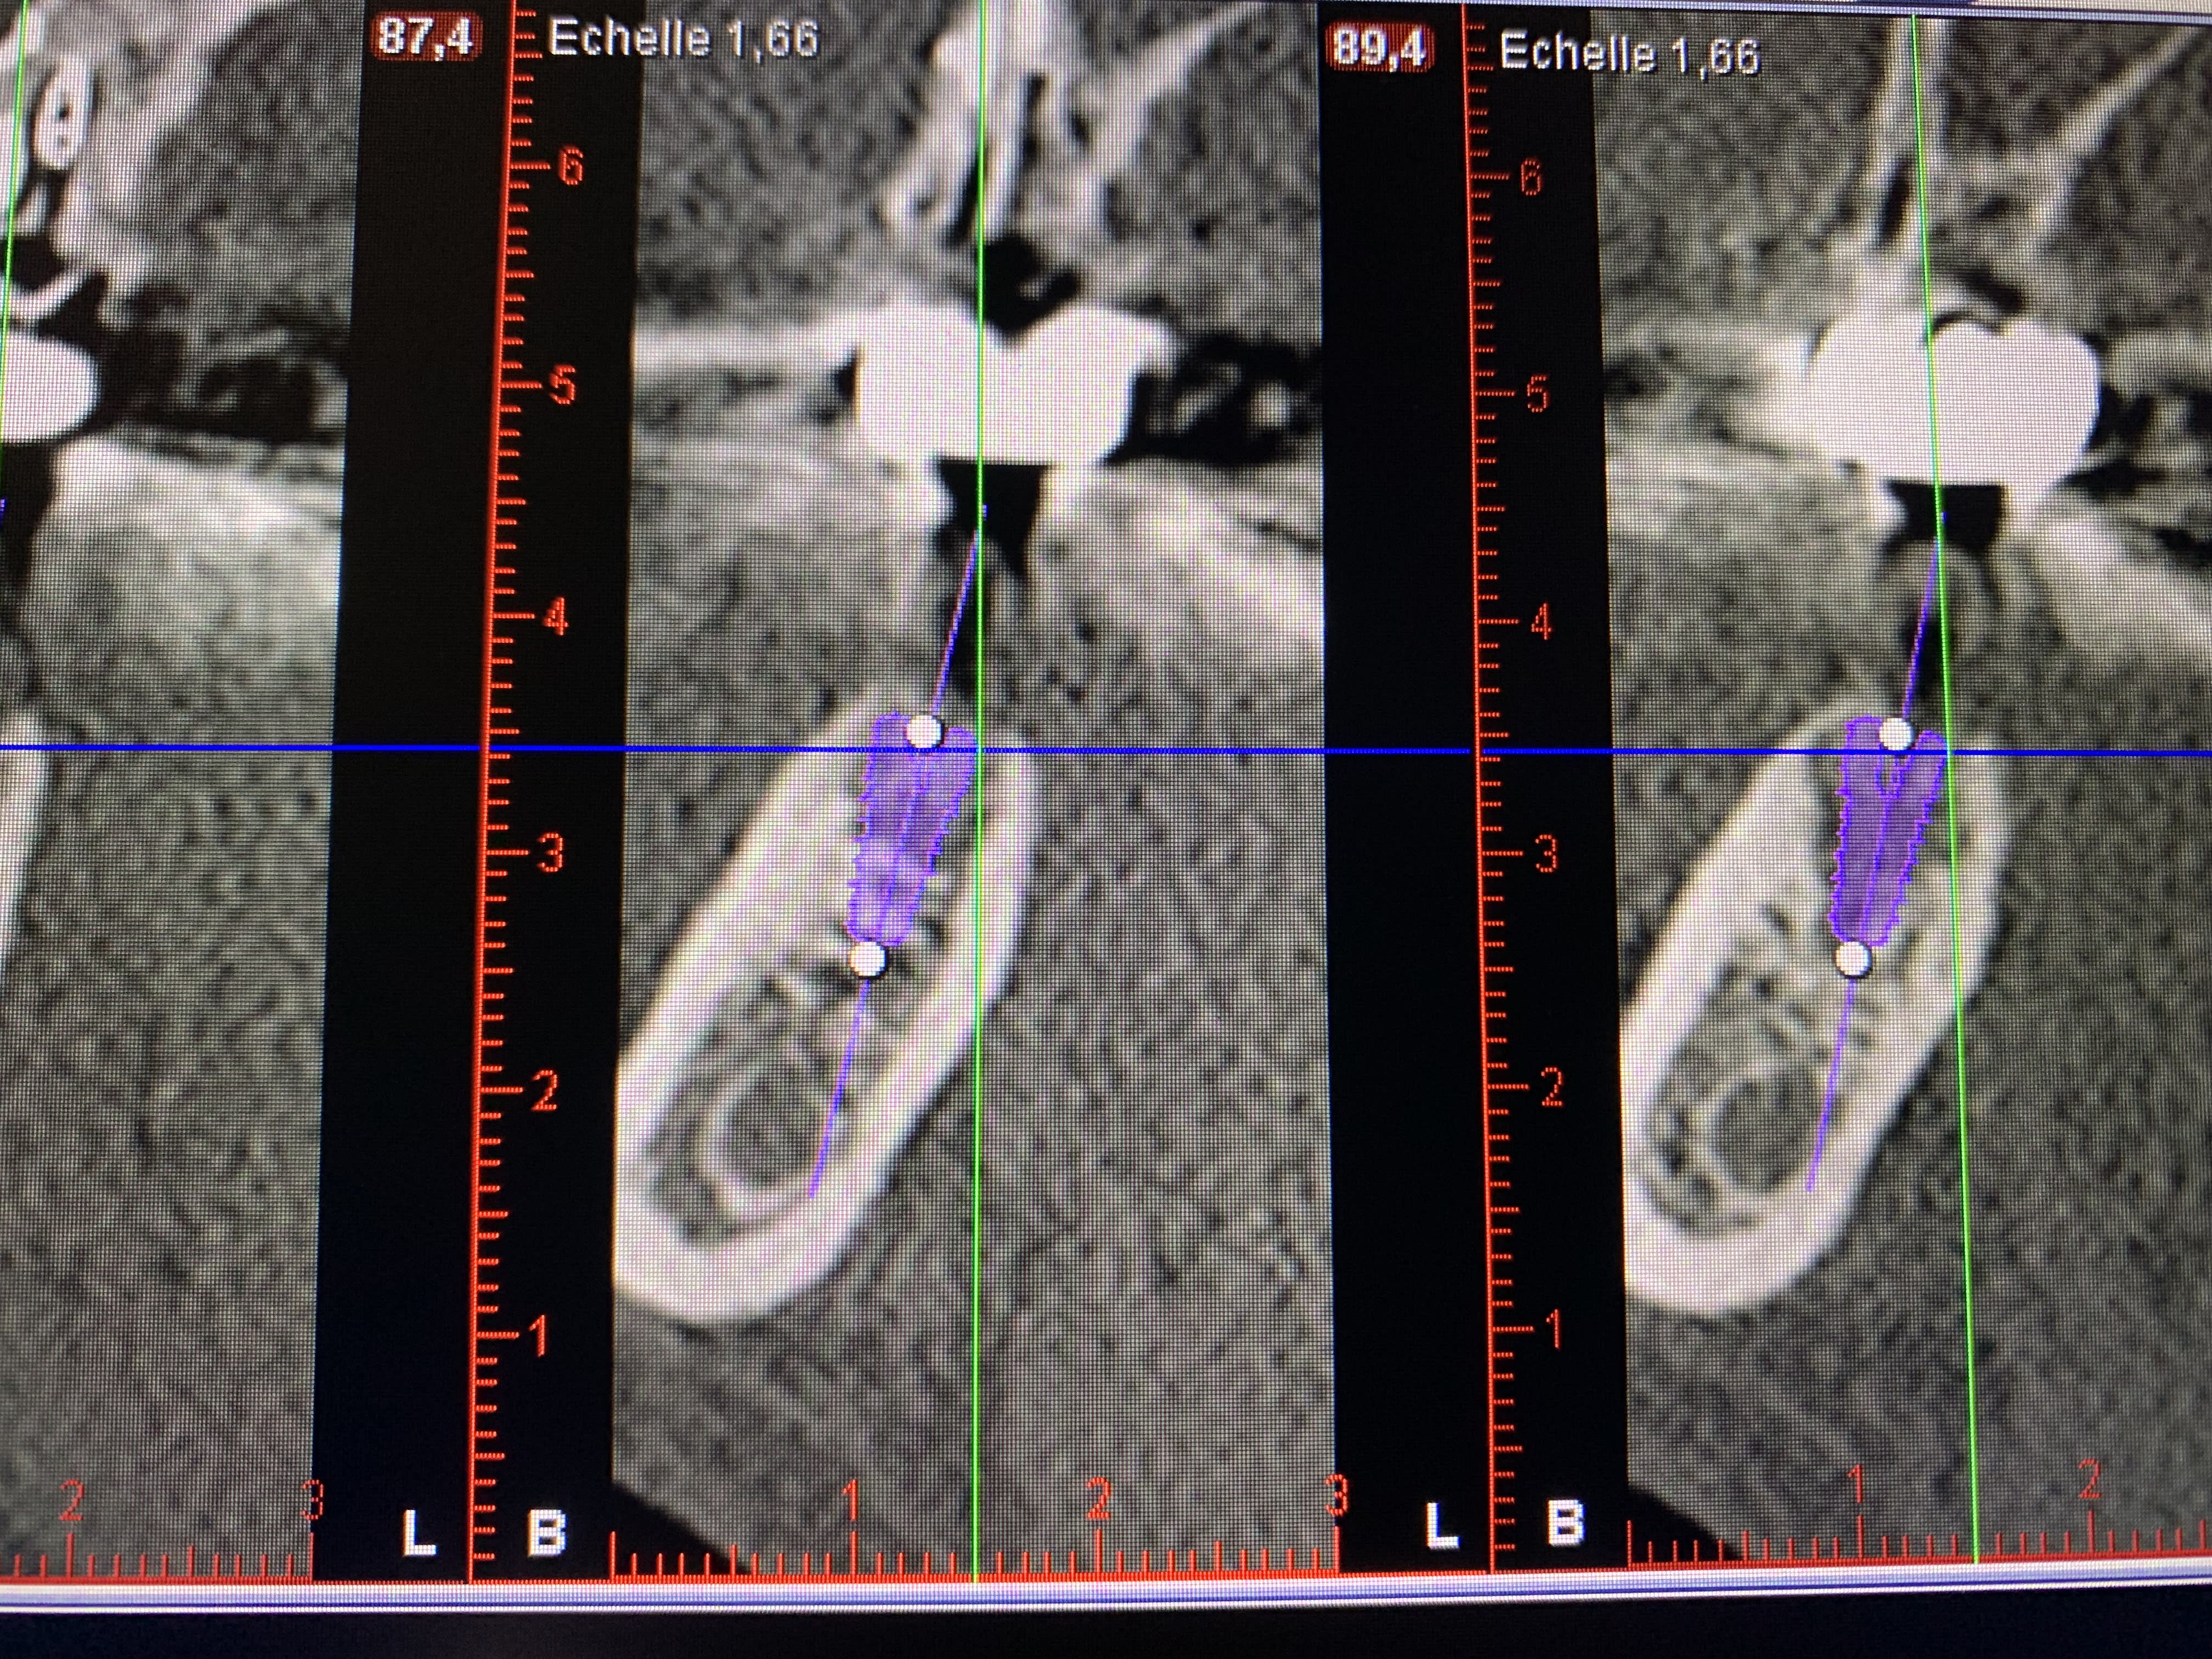

Vous me mettez grandeent le doute sur le choix de la taille mes implants ! Je ne comprends pas d’après le scanner en quoi cet implant est trop large, même si c’est peut-être juste je souhaiterais comprendre pour ne pas refaire la meme erreur.

Lundi j’en pose un autre, j’ai choisi 5 par 10 Parce que la molaire est très large. Ça vous paraît trop gros d’après le scanner ?